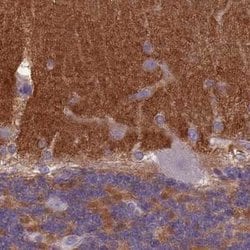

Invitrogen™ SLC8A2 Polyclonal Antibody

Brand: Invitrogen™ PA562250

| Immunohistochemistry (Paraffin) | |